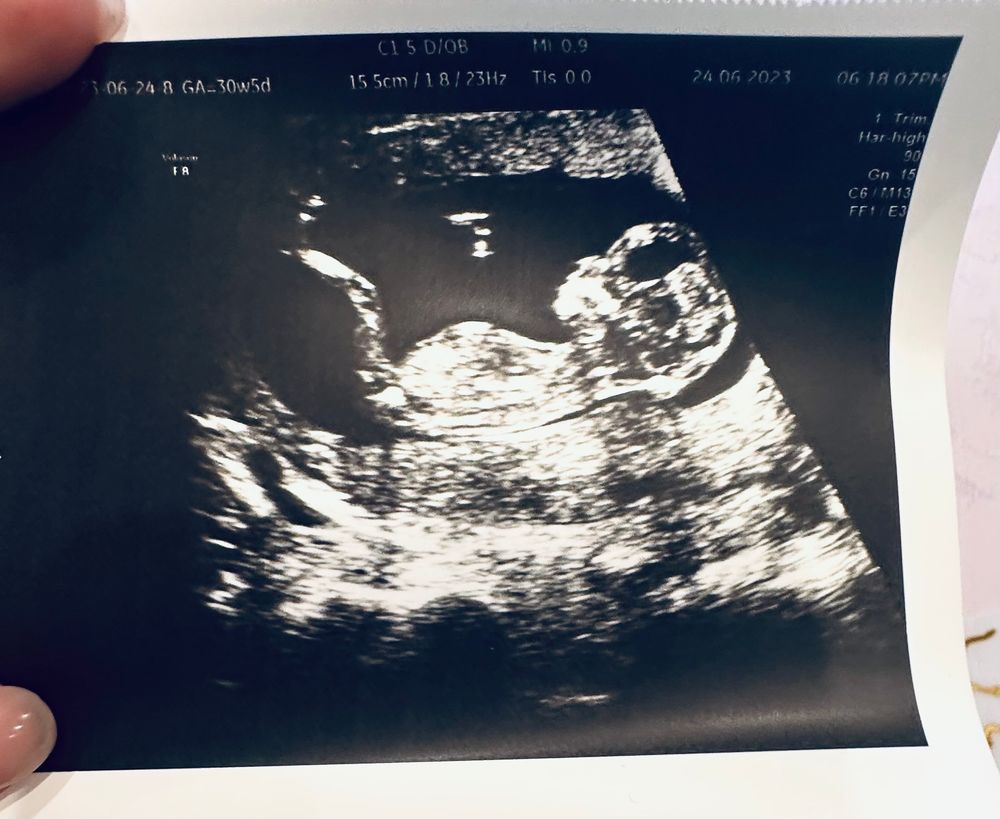

Меня оформили в регистратуре, было всего 2 человек, я и девушка. Отправили ждать к кабинету процедурному. Спустя 10 мин звучит моя фамилия, уточняют зачем я приехала? Я растерялась, ну вроде всё очевидно. Малышке поставили гипоплазию НК, риск СД 1:88. И врач с этого кабинета отправляет меня к врачам, меня начинают отговаривать, зовут заведующую. Заходит милая взрослая женщина и говорит, что последствия прокола выше, чем 1-2 % И у меня нет каких-то прям серьезных показаний, хотя всё может быть. НИПТ сдан и она видя фотографии с последнего узи малышки в профиль, говорит, что большие шансы на совершенно здоровую девочку. Узи сделанное мной в 3 раз в сроке (13+2), просто для альтернативного мнения уже нашло 2 косточки, я просила даже померить, 1.6 маловато, но хотя бы уже что-то, т.к на предыдущих 4 дня назад визуализация второй была слабая. Это видимо и стало решающим фактором, что с процедуры меня развернули. Обревелась, нанервничалась, выдохнула. Значит так должно быть.